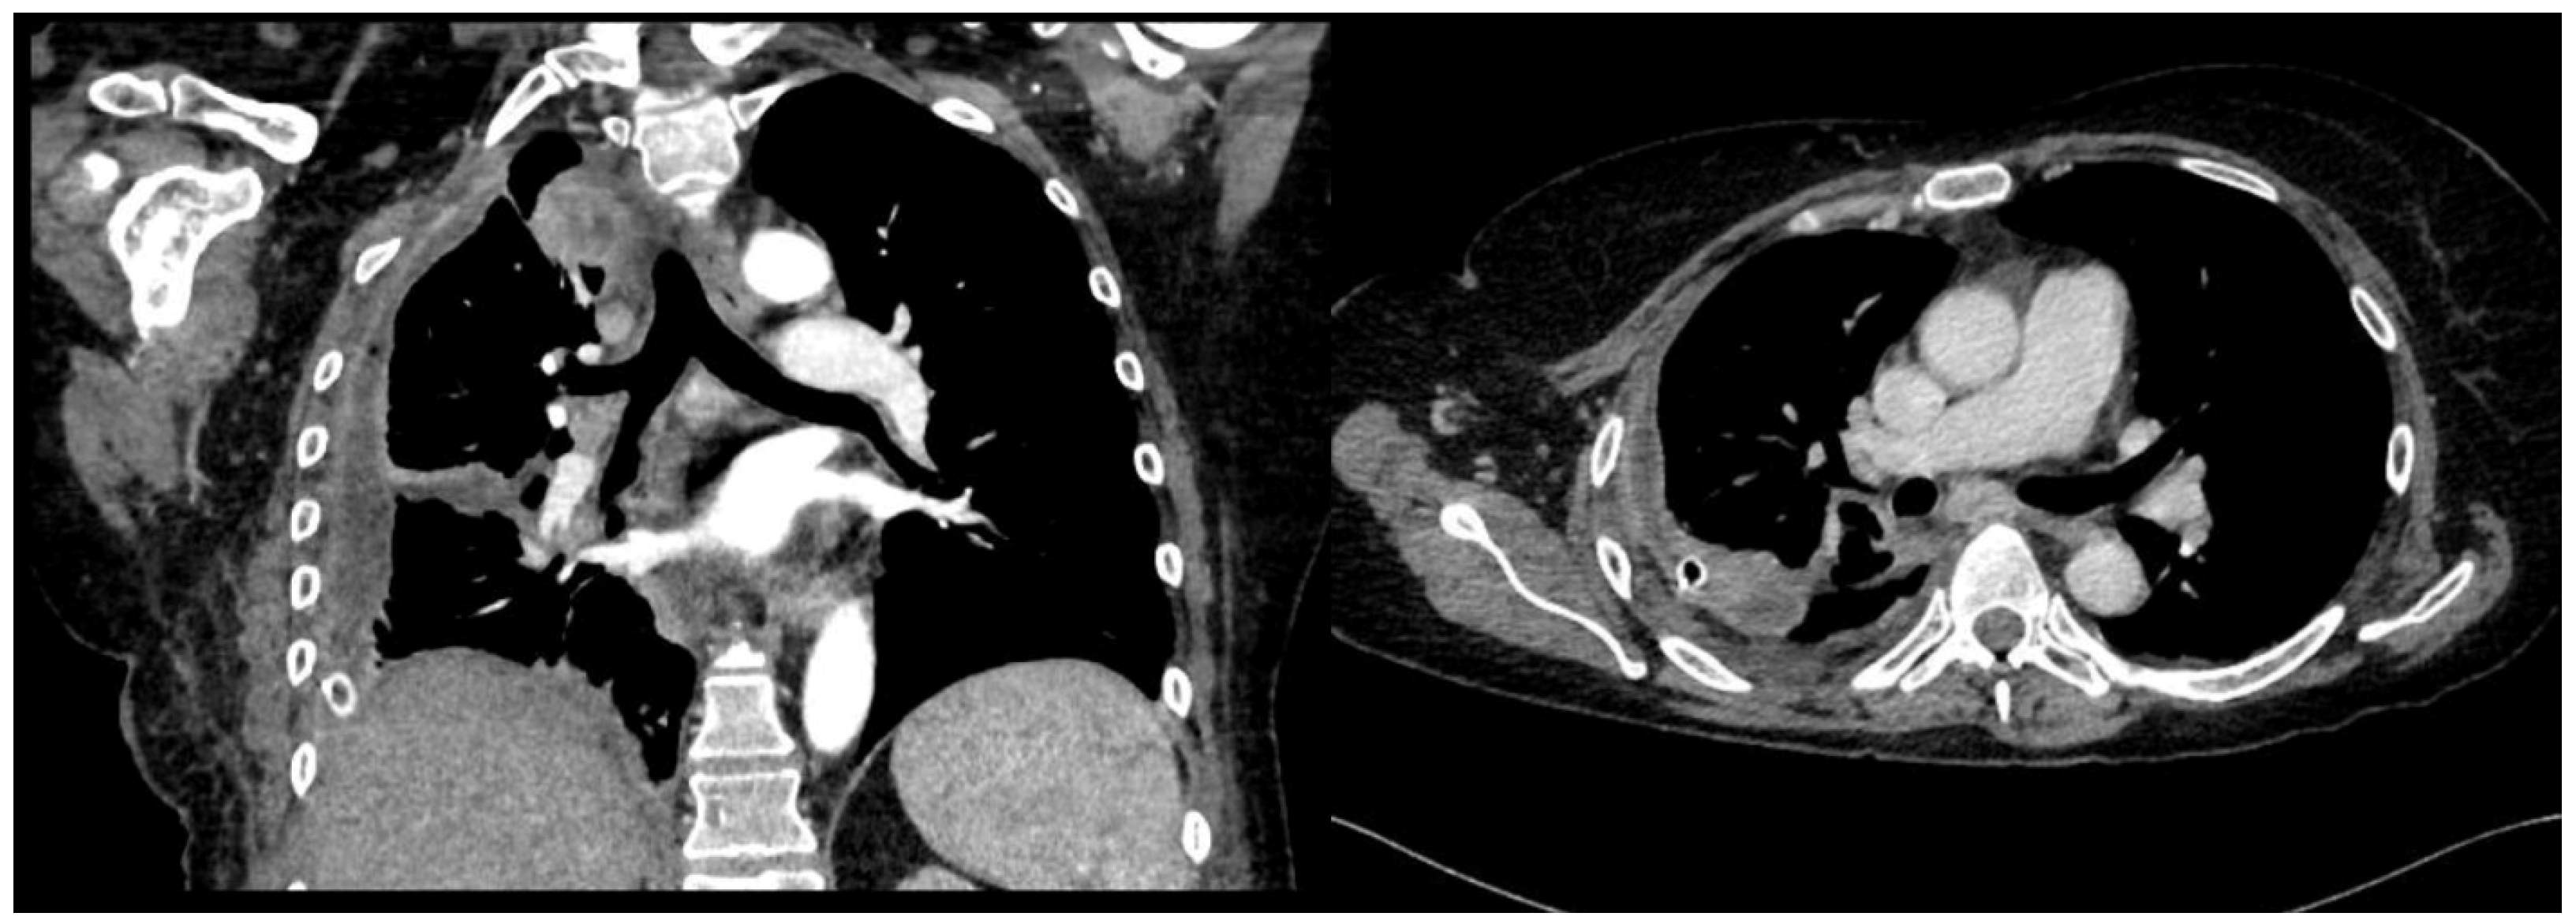

A 61-year-old female patient with obesity, discoid lupus, bipolar disorder, arterial hypertension, and hypothyroidism was admitted to our Respiratory Unit for respiratory failure and evidence of a large complex PEff on her chest CT, which also revealed complete atelectasis of the right lower lobe (RLL) and almost-complete atelectasis of the middle lobe (ML) and right upper lobe (RUL) (Figure 6). There was also a solid tissue surrounding the right main bronchus and its main branches, which was suspected to be neoplastic. It had a central hypodense area consistent with necrosis.

Peripheral enhancement of the pleural layers was also observed.

Figure 6. Chest CT scan of the mediastinal window in the coronal (A) and axial (B) plane, showing a large right pleural effusion, occupying almost the entire hemithorax with organized appearance. There is also a complete right lower lobe atelectasis and almost-complete right middle and upper lobe atelectasis with sparing of anterior sectors.